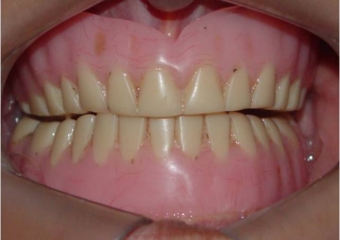

Imagem inicial